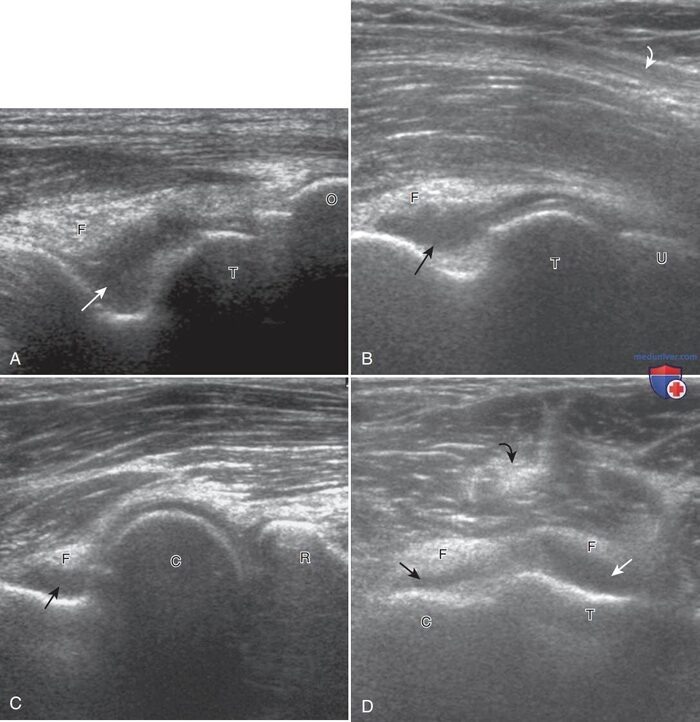

УЗИ - отличный метод для безопасной диагностики, признаком подагры является “двойной контур” - отложение кристаллов мочевой кислоты на суставном хряще, “снежная буря” - скопление кристаллов в суставной полости. Если это видно при исследовании, диагноз почти "в кармане", но, к сожалению, такая картина визуализируется не всегда.

При пирофосфатной артропатии - кристаллы, как правило, внутри хряща. При гидроксиаппатитной артропатии - внутри мягких тканей вокруг сустава, как правило, сухожилия. МРТ - обычно малоинформативно Лечение: снятие приступа и устранение накопленных запасов кристаллов (применимо только для подагры).